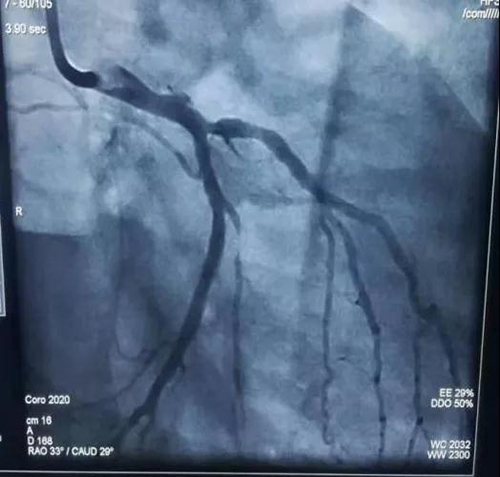

7月22日是Andrwe的生日,但是老天却跟他开了一个不大不小玩笑。这天早上,他感到持续的胸痛,并且伴有后背的不适,开始并没有在意,但是随着症状的加重,他预感到了严重性,到基奎特心脏病研究所就诊,心电图示V1-4 ST段抬高,结合心肌酶的情况,诊断为急性前壁心肌梗死。苑海涛教授得知病人情况后,组织中国专家组,立即对患者实施经桡动脉急诊冠状动脉粥样硬化造影术,并成功开通了患者闭塞的左前降支,植入1枚支架。这是坦桑尼亚国内首例经桡动脉急诊冠状动脉造影术+支架植入术。生日重获新生,Andrwe眼含热泪,向中国专家团队竖起了大拇指,表达了他由衷的感激之情。

患者术前造影情况

患者术后造影情况